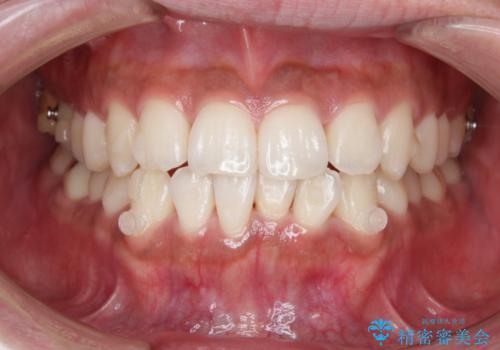

- 上下の前歯のがたつきが気になるとご相談にいらした方です。光加速矯正装置(オルソパルス)を用いて短期間で仕上げることが出来ました。

一般的に噛む力が強い方は矯正治療に時間がかかると言われてます。光加速矯正装置(オルソパルス)を用いることで短期間で仕上げることができました。